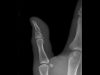

Medic specialist – rezonanță magnetică, cu focus pe imagistică musculo-scheletală